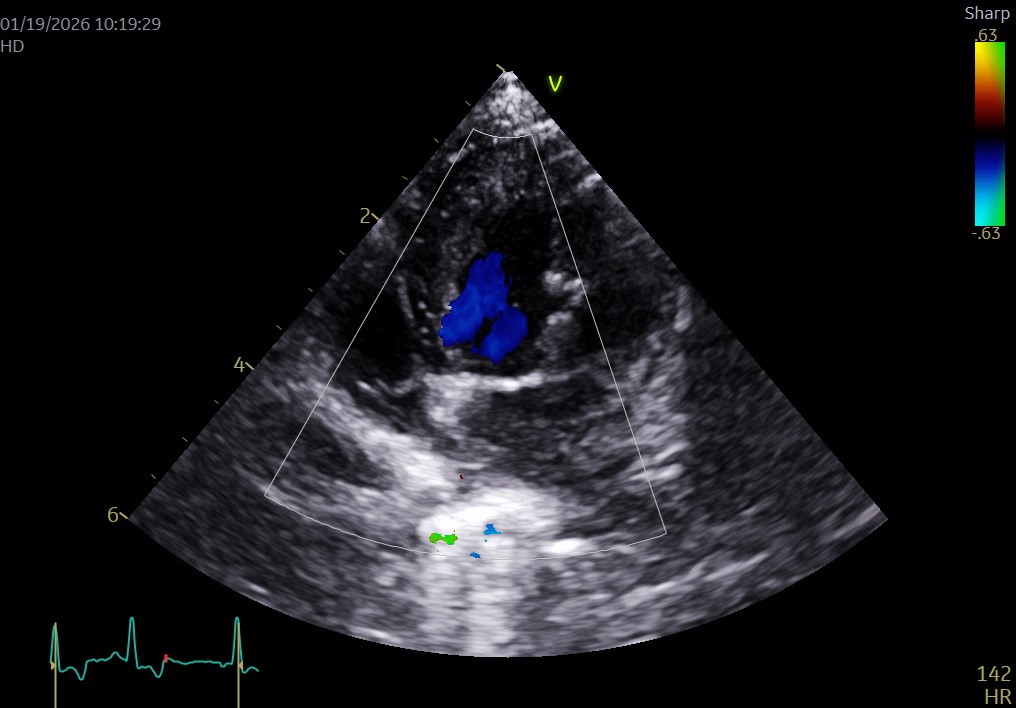

▲同上(術後1ヶ月)

手術直後は血圧、心拍数、点滴量や尿量など循環を細かく整えて心臓が回復するのを待ちます。不整脈や出血がないことを確認し、超音波検査を繰り返して心臓の変化に合わせて点滴や内服を調整します。

特に術後3日間は手術による合併症の危険が高い時期に当たり、炎症、貧血、出血、急性腎不全、膵炎、不整脈、血栓症などの危険があります。介入の程度を図りながら回復を待ち、回復傾向にあることが確信的になると退院が可能になります。本症例は術後安定して推移したため、抗菌薬、制吐薬、抗血栓薬、強心薬(ピモベンダン)などの内服を処方して術後4日目に退院しました。